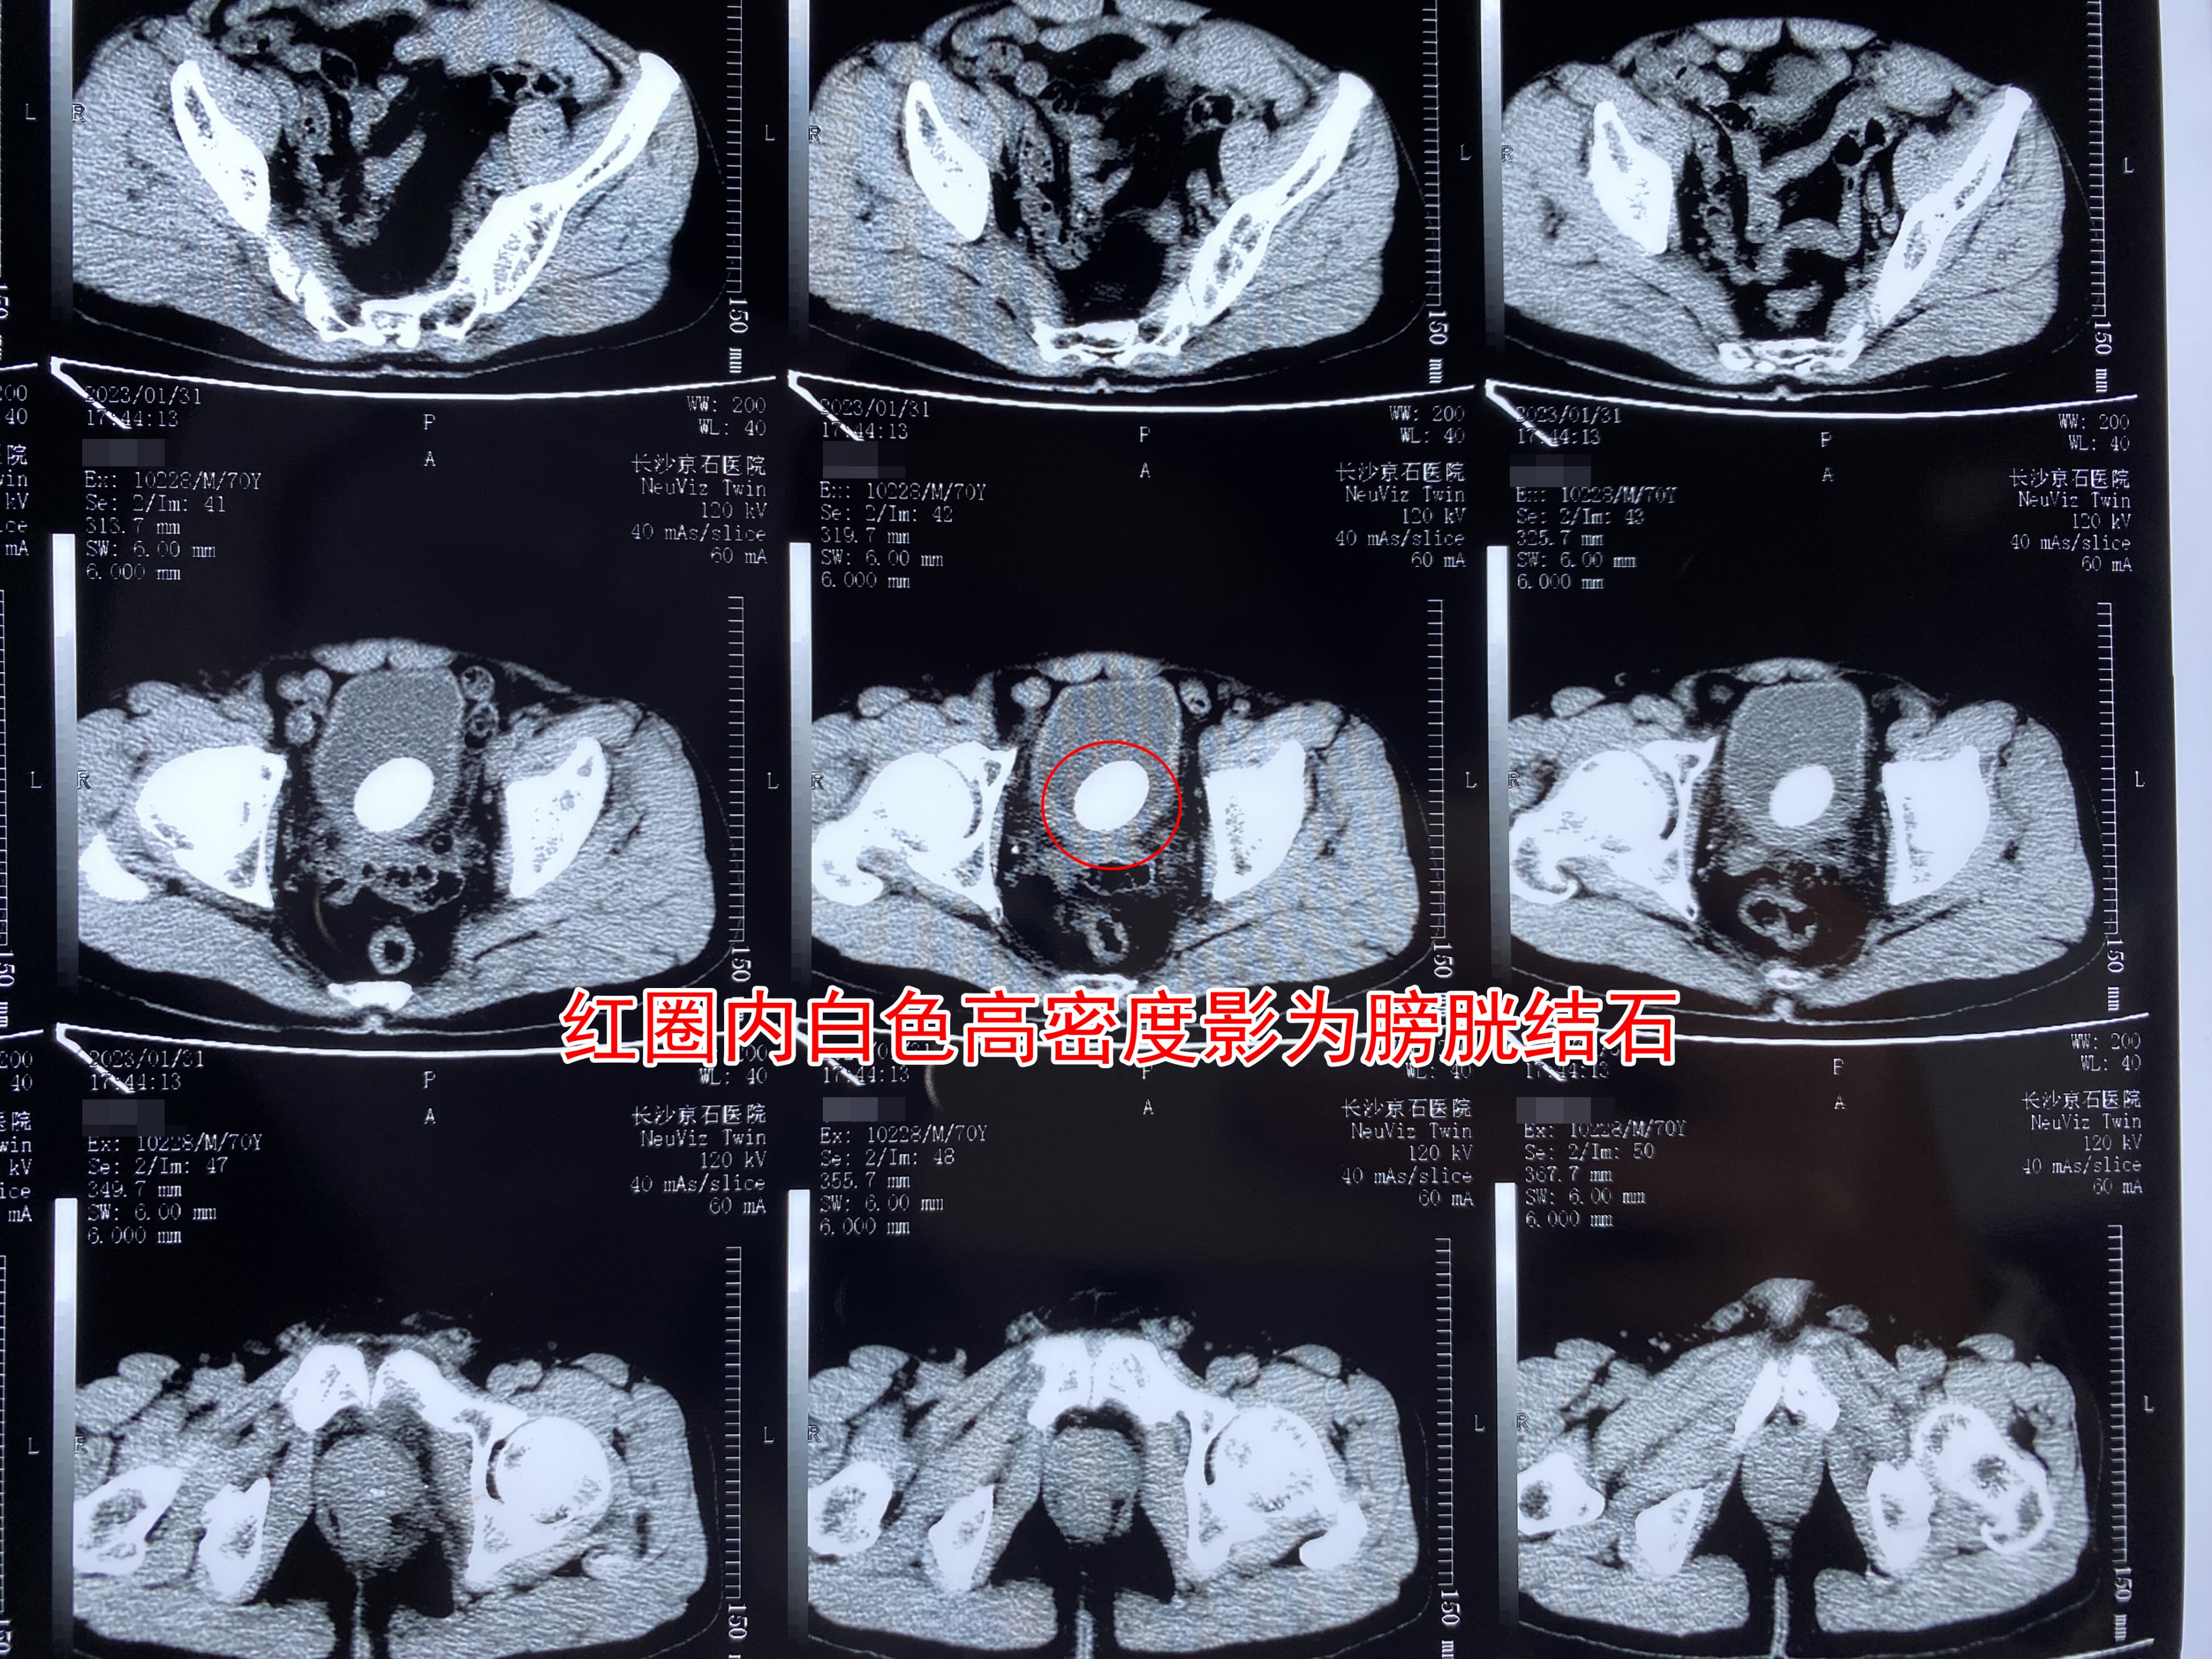

(刘嗲嗲术前CT检查结果局部图)

1月31日,刘嗲嗲在长沙京石医院接受了初步检查,确诊患有膀胱结石,且结石大小已达4*3公分,急需进行手术处理,于是刘嗲嗲立即办理了入院手续,等待后续手术治疗。